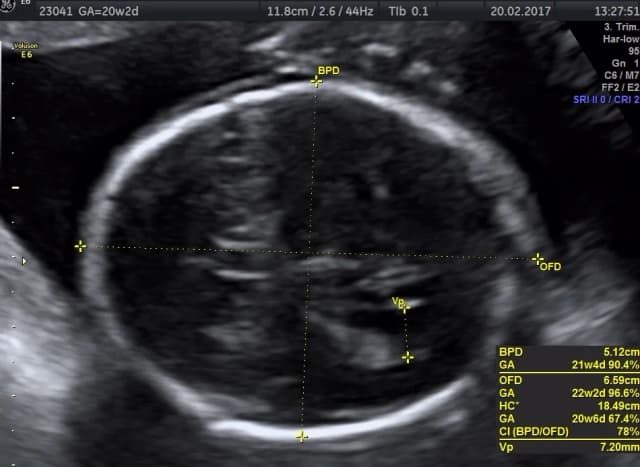

Tag ii trymestr ciąży